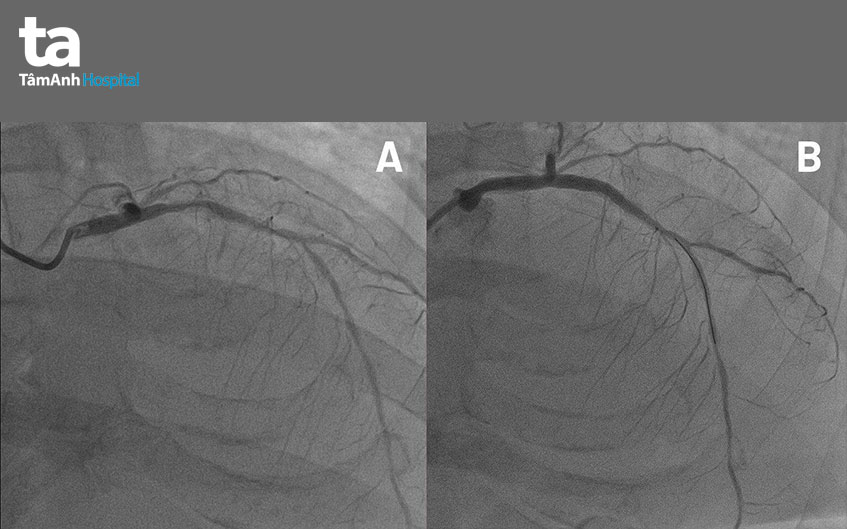

Sau 24 giờ điều trị, tình trạng bệnh nhân không cải thiện, các bác sĩ BVĐK Tâm Anh TP.HCM tiếp tục hội chẩn, quyết định chụp và nong mạch vành cứu bệnh nhân, sau đó lọc thận hỗ trợ. Kết quả chụp mạch vành cho thấy, trong số ba nhánh động mạch nuôi tim, hai nhánh chính (động mạch mũ và động mạch vành phải) đã tắc hoàn toàn. Nhánh còn lại, động mạch liên thất trước hẹp đến 78-80%. Tình trạng khá phức tạp, điều trị nội khoa bằng thuốc không đạt hiệu quả nếu không can thiệp ngay”.

Một ngày sau khi được chăm sóc và điều trị tích cực tại khoa cấp cứu, bà Minh được BS.CKII Huỳnh Ngọc Long – Giám đốc Trung tâm Can thiệp Mạch tiến hành chụp và can thiệp nong động mạch vành. Nhờ hệ thống chụp mạch máu Philips Azurion Robotic Ceiling FlexArm với cánh tay robot xoay 360 độ quanh người bệnh, bác sĩ có thể tiến hành kỹ thuật chụp mạch vành Cardiac Swing, chỉ cần 2 lần chụp với tổng cộng 7-8 ml thuốc cản quang đã thu được kết quả tối ưu thay vì phải chụp 6-8 góc độ như thông thường.

Theo bác sĩ Long, kỹ thuật nong mạch vành phải tiến hành nhiều lần, mỗi lần thật nhanh (2-3 giây) nhằm tránh tình trạng huyết áp tụt không xử lý kịp. Kết quả là sau vài lần nong, mạch máu hẹp được mở rộng, tạo điều kiện thuận lợi để đưa đoạn stent đường kính 3,5mm vào động mạch liên thất trước. Thủ thuật kết thúc thành công, mạch máu nuôi tim thông trở lại, cứu sống bệnh nhân trong gang tấc.